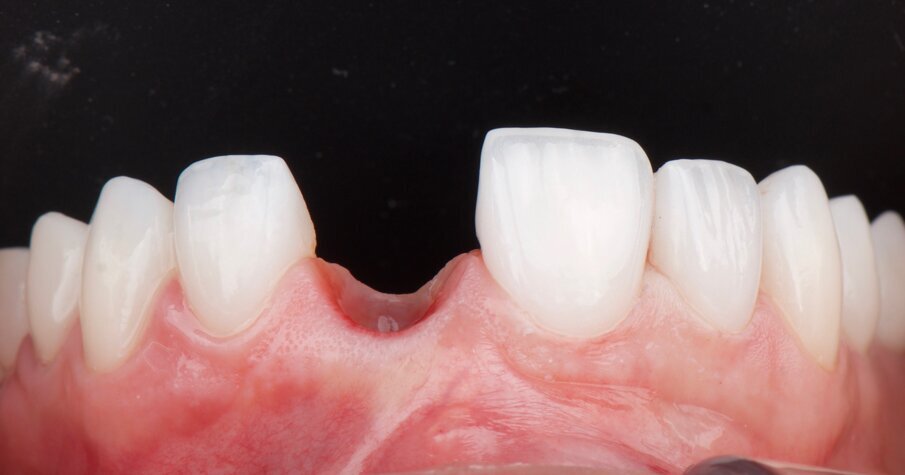

The tooth was removed atraumatically (Fig. 3) with sectioning of the root, and the socket was debrided. No flap was elevated, and the buccal bone plate was intact after tooth extraction. A xenograft material (Geistlich Bio-Oss, Geistlich Pharma) was placed inside the extraction socket and covered with a non-cross-linked collagen membrane (Fig. 4). A periapical radiograph was taken after socket preservation and showed that the bone substitute material was acting as a scaffold (Fig. 5). A provisional acrylic Maryland bridge was placed as a temporary aesthetic and functional solution (Fig. 6).

Fig. 4: Grafting material placed into the extraction socket and covered with a non-cross-linked collagen membrane.